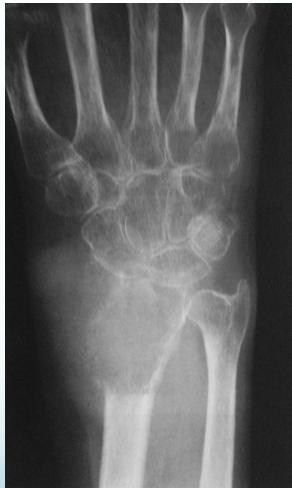

Aneurysmal Bone Cyst

- Child - young adult

- Metaphysis of long bone

- X-ray:

- Well-defined cyst

- Trabeculated

- Eccentrically placed

- Ballooning

- Bloody content

- Treatment:

- Curettage and bone graft

- Metaphysis, Eccentric

Comparison of Cyst-Like Lesions in Bone

- At metaphyseal side of physis

- Expansile